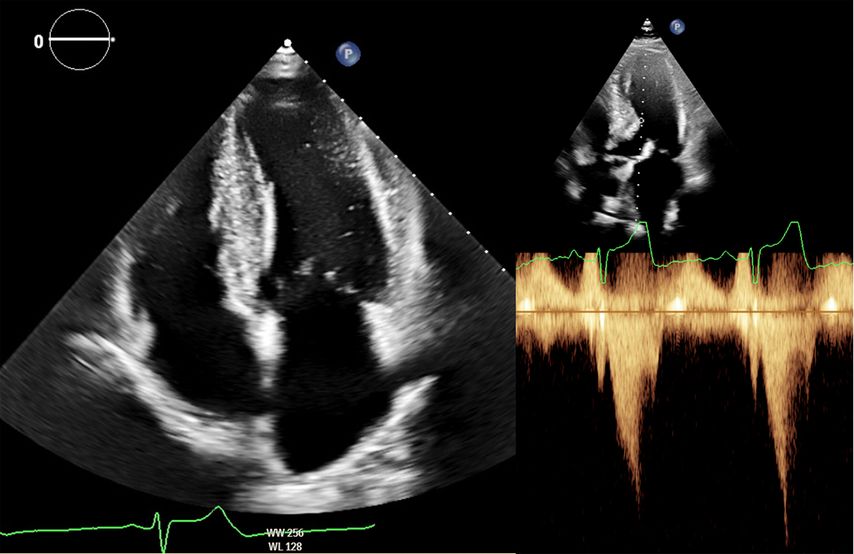

Abb. 2: Echokardiografie bei HOCM mit 4-Kammer-Blick (links) und Obstruktion im Ausflusstrakt (rechts)

Dennoch ist die Echokardiografie aufgrund der niederschwelligen Verfügbarkeit als erste Untersuchungsmodalität und zur Verlaufsbeurteilung nicht wegzudenken. Mit der Ejektionsfraktion, der Vorhofgröße und der Beurteilung der diastolischen Funktion können prognostisch wichtige Parameter erhoben werden. Ein „apical sparing“ in der Analyse des myokardialen Strains oder der Aspekt eines „granular sparkling“ kann einen Verdacht auf kardiale Amyloidose begründen (Abb.3). Jede echokardiografische Untersuchung wegen des Verdachts auf LVH sollte außerdem eine Bestimmung des LVOT-Gradienten inkl. Valsalva-Manöver beinhalten (Abb.2).